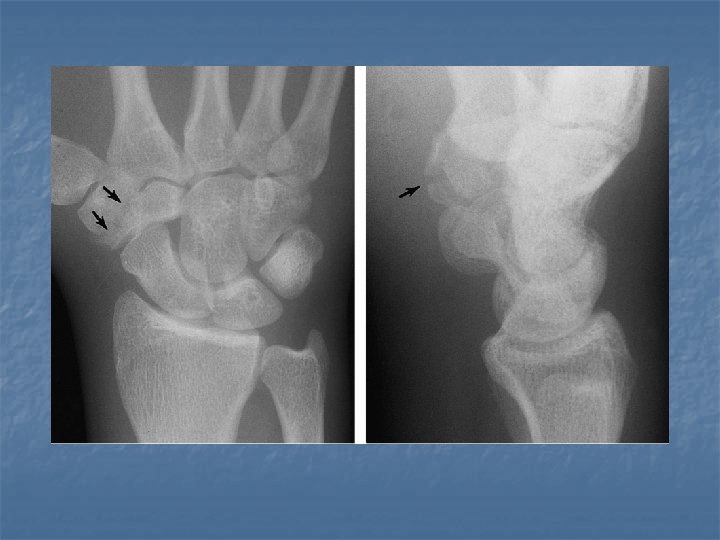

Fracture of triquetral n n Usually a subtle fracture Best seen in the lateral or pronated oblique view.